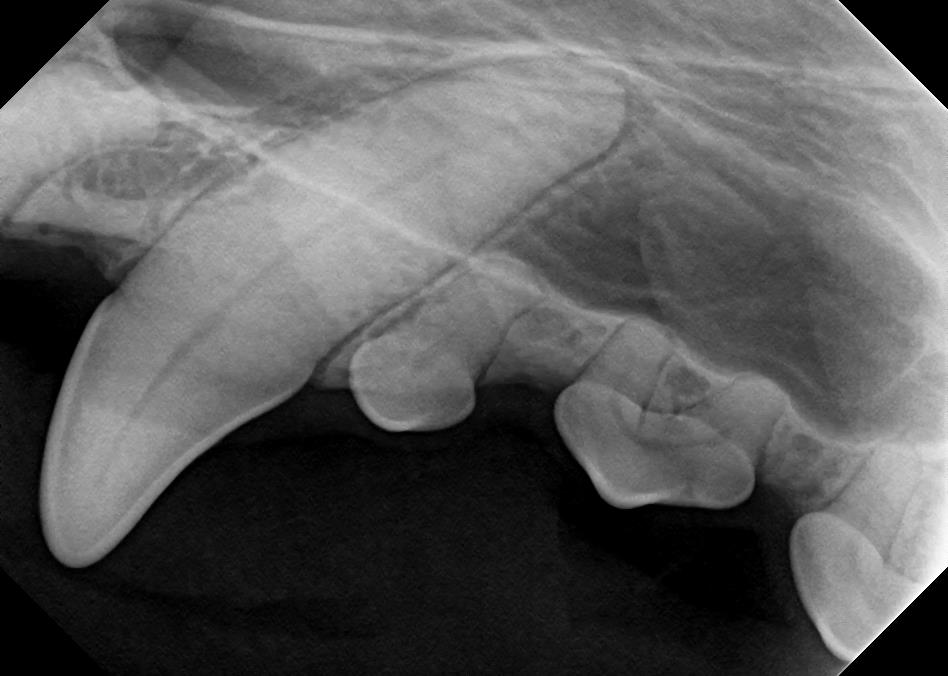

Examples of healthy teeth:

At A Couple of Vets, our animal hospital staff is well-versed in the latest dental cleaning techniques to remove plaque and tarter from the teeth’s surface as well as from below the gum line. We perform dental x-rays at every cleaning to ensure that the teeth are completely healthy. They may look good on the surface, but many problems occur below the gum line and are only visible with x-rays.